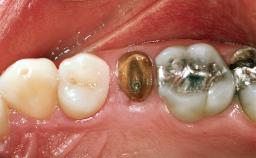

This 65-year-old female patient presented for implantbased restoration of the maxillary posterior region (25–27). Although this patient was free of medical compromise, her treatment was associated with several modifying factors. She had been a patient of record in the practice for more than twenty years. Her initial treatment included extraction of the failing maxillary left first molar, and restoration with a fixed dental prosthesis (25–27) and crown (24). At the time of initial restoration, implants were not considered appropriate options for the replacement of single posterior teeth.